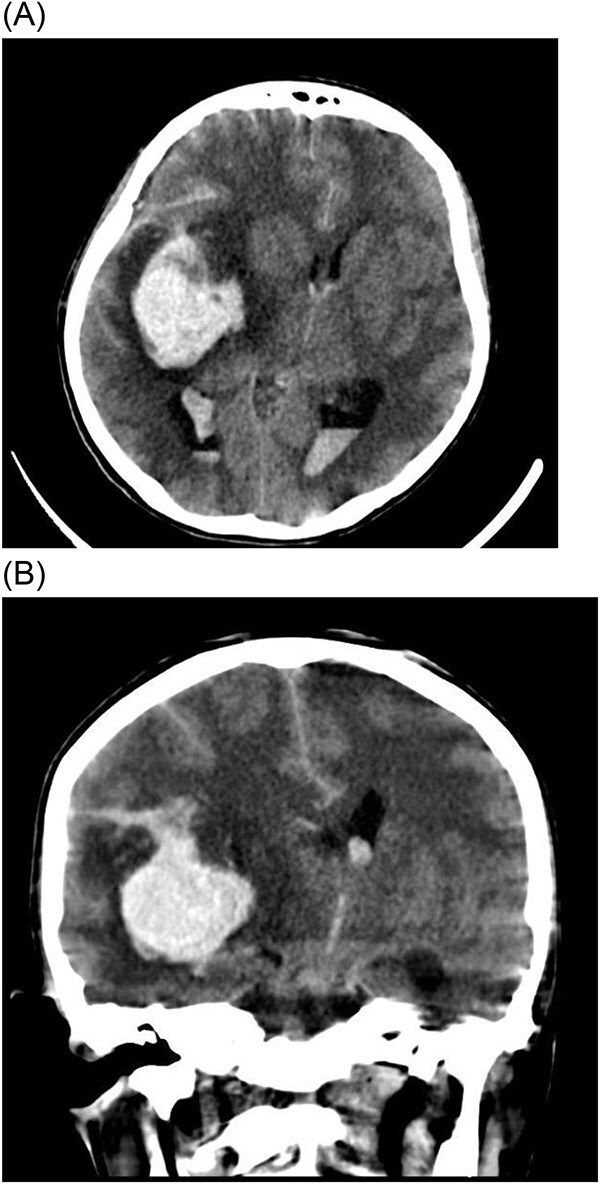

霉菌性动脉瘤(MAs)是感染性心内膜炎(IE)的一种罕见但危及生命的并发症,由感染性心内膜炎栓塞在脑血管内引起并导致动脉瘤形成。本病例报告描述了一名17岁女性在IE治疗期间出现多发性MAs,导致灾难性的神经功能衰退和最终死亡。在接受开胸手术切除植物后,患者因真菌性动脉瘤破裂出现颅内出血,在一次不成功的开颅减压手术后死亡。该病例强调了在IE背景下早期识别和及时干预MAs管理的重要性,以及需要制定方案来改善这些高危患者的预后。MAs破裂相关的高死亡率突出了这些并发症的严重性及其管理的挑战。

Mycotic aneurysms (MAs) are a rare but life-threatening complication of infective endocarditis (IE), resulting from septic emboli lodging in cerebral vessels and leading to aneurysm formation. This case report describes a 17-year-old female who developed multiple MAs during treatment for IE, resulting in catastrophic neurological decline and eventual death. After undergoing open-heart surgery for vegetation excision, our patient then developed intracranial bleeding due to mycotic aneurysms rupture, which led to her death after an unsuccessful decompressive craniotomy. This case highlights the importance of early recognition and timely intervention in the management of MAs in the context of IE, as well as the need for protocols to improve outcomes in these high-risk patients. The high mortality rate associated with ruptured MAs highlights the critical nature of these complications and the challenges in their management.